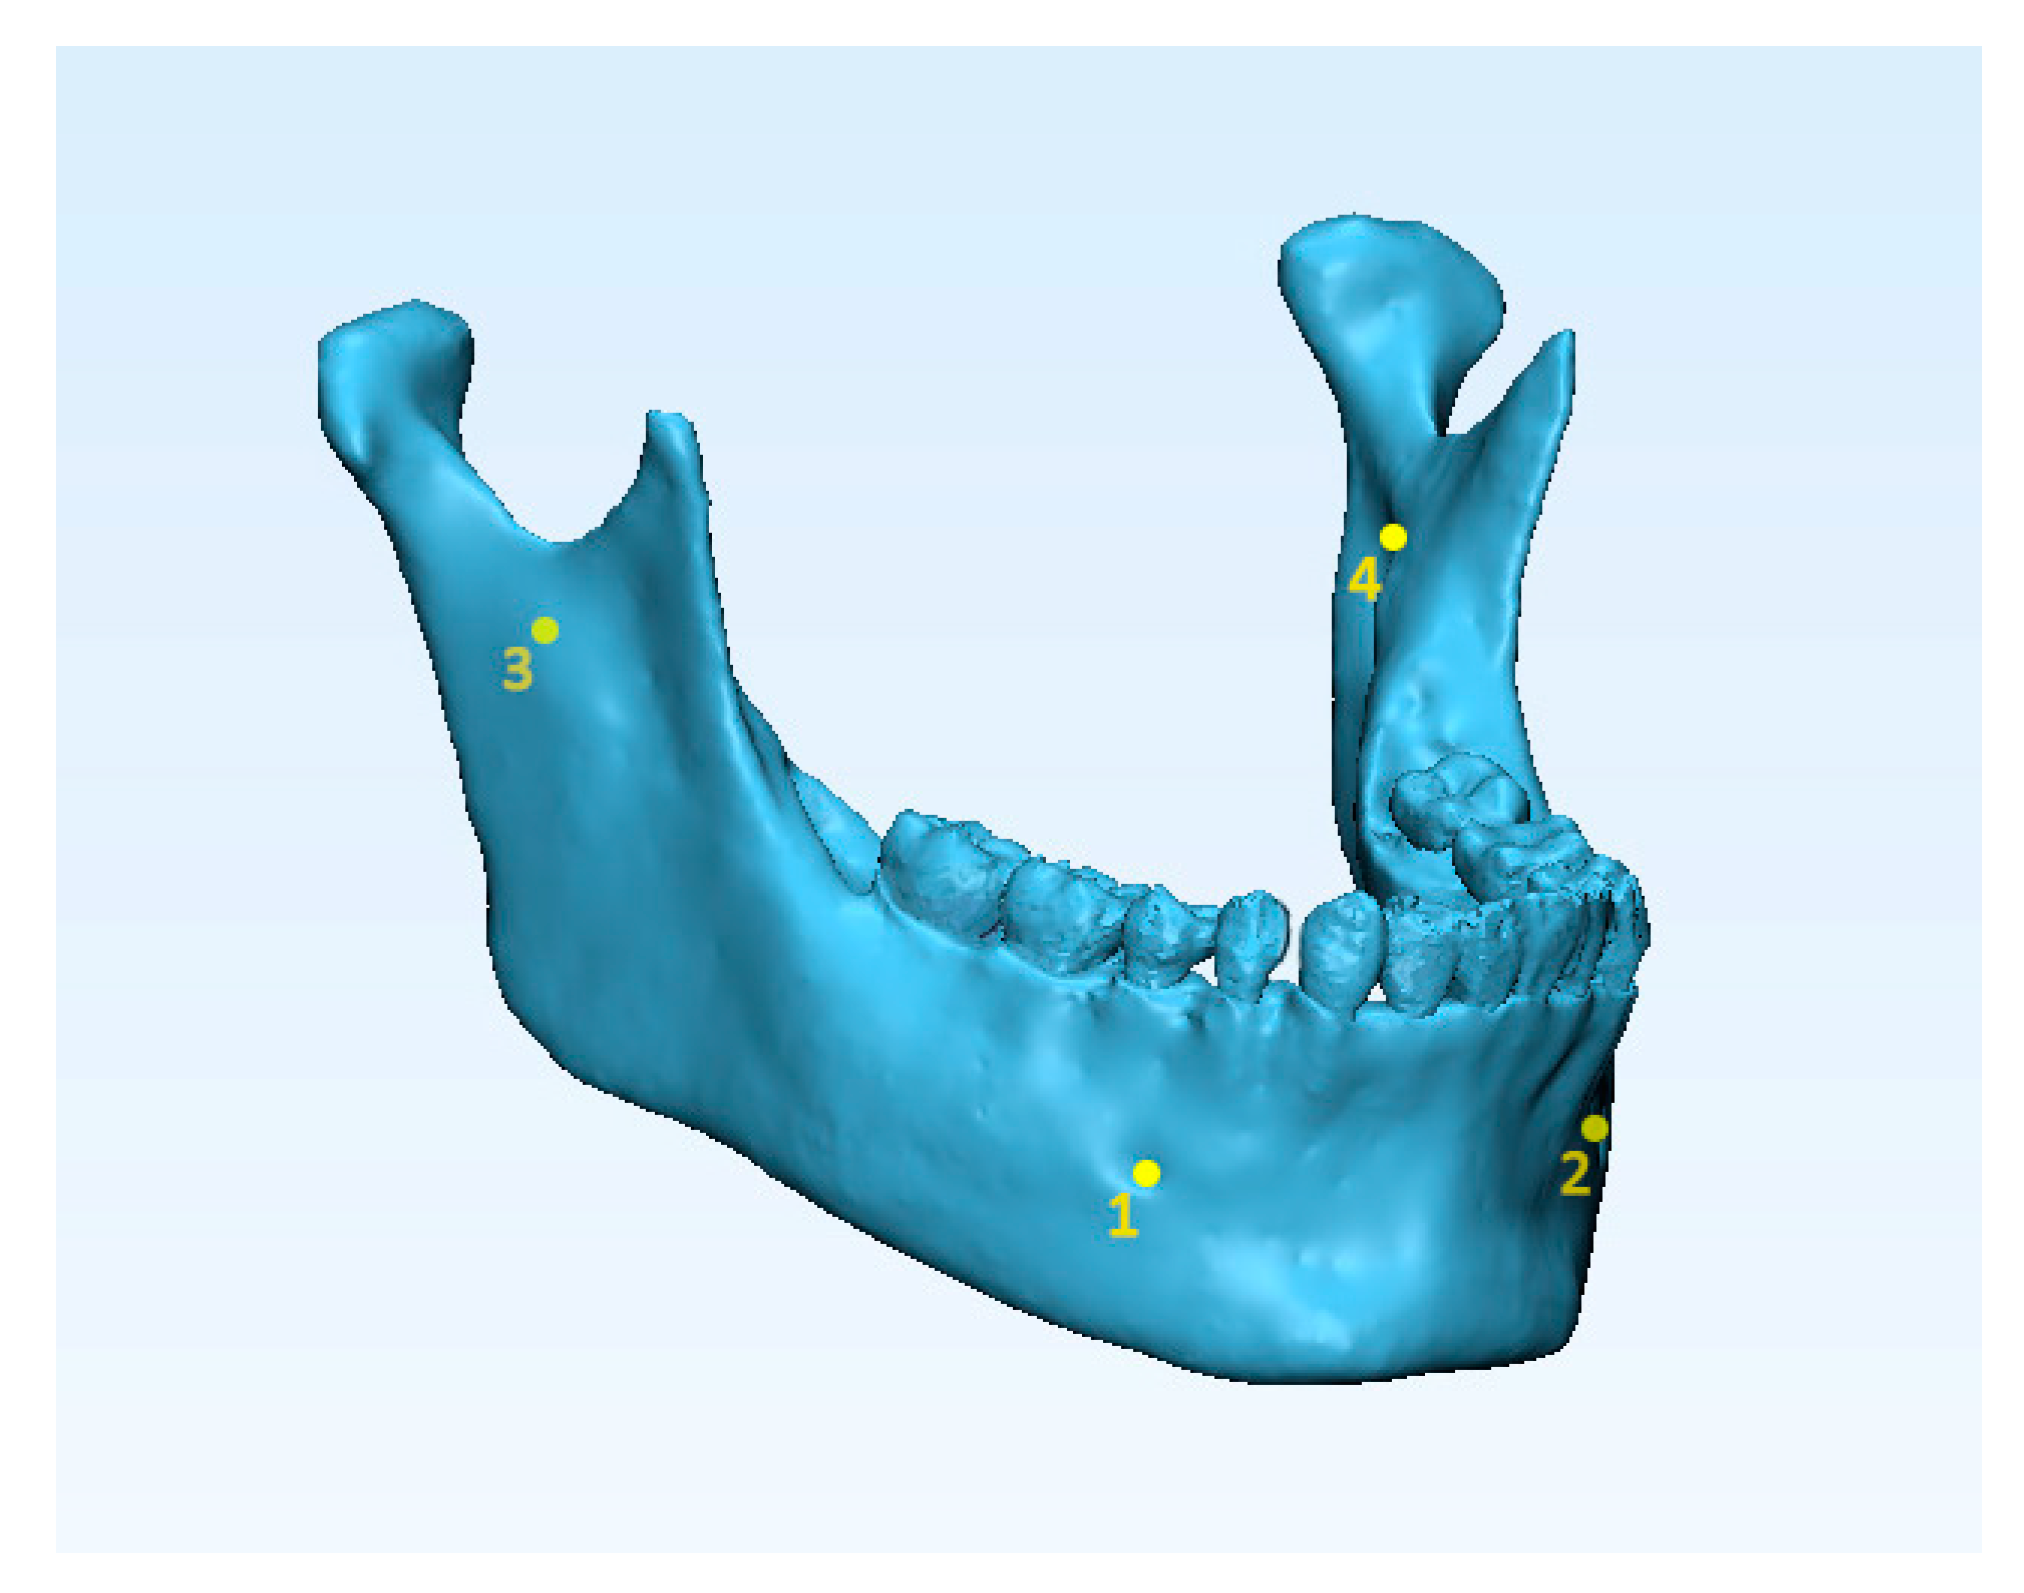

2. Materials and Methods